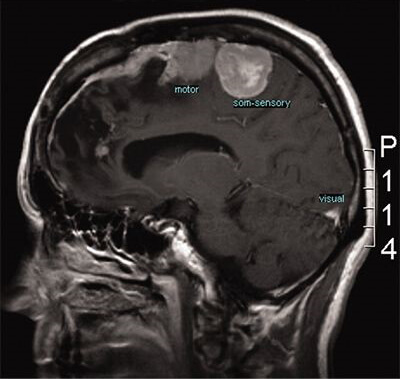

Cercetările sugerează că utilizarea terapiei hiperbarice (HBOT) împreună cu radioterapia sau chimioterapia poate avea rezultate semnificative în reducerea mortalității și a recidivelor. HBOT poate contribui la tratarea cancerului prin mai multe modalități, cum ar fi îmbunătățirea fluxului sanguin către tumoare, încetinirea creșterii celulelor canceroase (în special celulele canceroase hipoxice, care au un conținut scăzut de oxigen) și creșterea eficacității terapiei standard.

De asemenea, HBOT poate ajuta și la reducerea efectelor secundare ale tratamentului cancerului, cum ar fi greața, vărsăturile și oboseala.